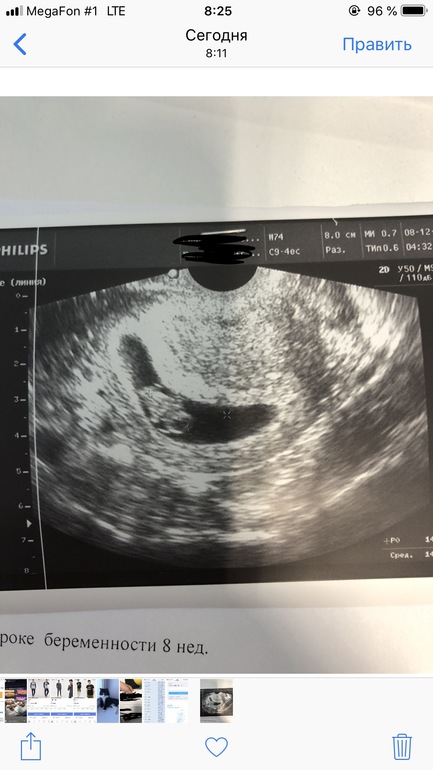

Я за это поняла, но девочки в комментариях на прошлый пост написали что не может быть размер пя быть меньше ктр ,попросили фотографию , просто в комментариях она не загружается ,по фотографии вроде не похожи что размер пя такой уж маленький

Я тоже думаю что это невозможно,узи через неделю будут делать ,гинеколог мне сказал что забыли третие значения поставить что бы понять какой пя, а пя же на фотографии видно в чем он находиться,вроде по виду там места хватает, а так получается написано якобы пя 10 мм если взять средний диаметр.

Все равно маленькое выходит,я думаю что врач ошиблась с размером ПЯ У меня в 5+1 неделю вот такое было ПЯ 14х9х10 мм

Самара

По фото теперь видно) вам третий размер действительно не указали, получается плодное яйцо достаточно длинное, но "сплюснутое ", вероятно из-за тонуса стенок матки. Лечите тонус с гинекологом, через неделю уз-контроль. Пусть все будет хорошо!

Спасибо вам, в больницу положили колят, а так видно же по фото что место хватает куда расти?

Видно конечно, пя длинное, место есть, дай Бог тонус снимут и оно более физиологичную форму примет